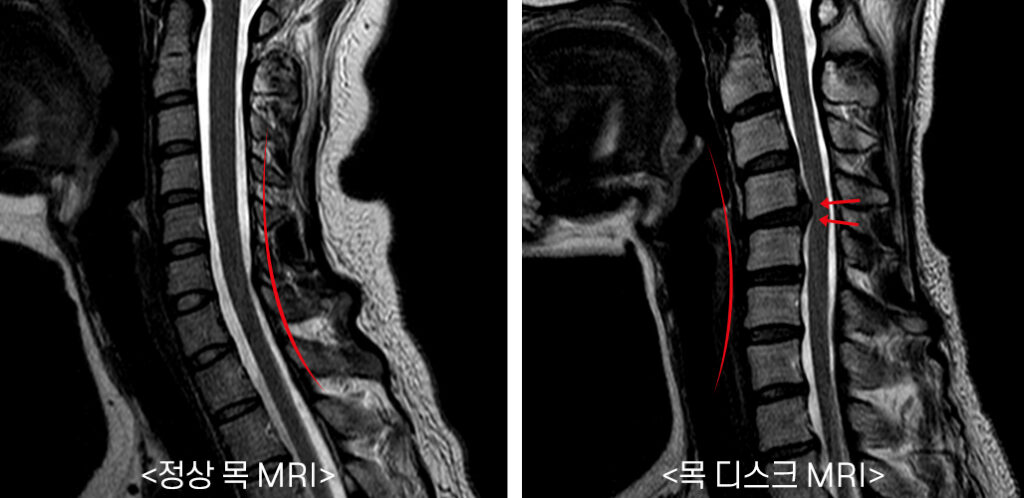

목 디스크 증상 총 정리 중 원인이고요. 한방 의학정보에 의하면 목 디스크는 목 뼈 사이 추간판이 파열됐거나 탈출되어 경추 신경의 자극, 압박으로 인하여 목, 어깨, 등, 팔 등 통증과 신경학적 증상이 있는 질환이예요.

경추는 제일 위쪽 목에 있는 7개의 뼈이라고 합니다. 경추는 운동성이 크므로 경추의 추간판은 압력에 의해 탈출되어 척수, 신경근을 억압되게 된다 하였습니다.